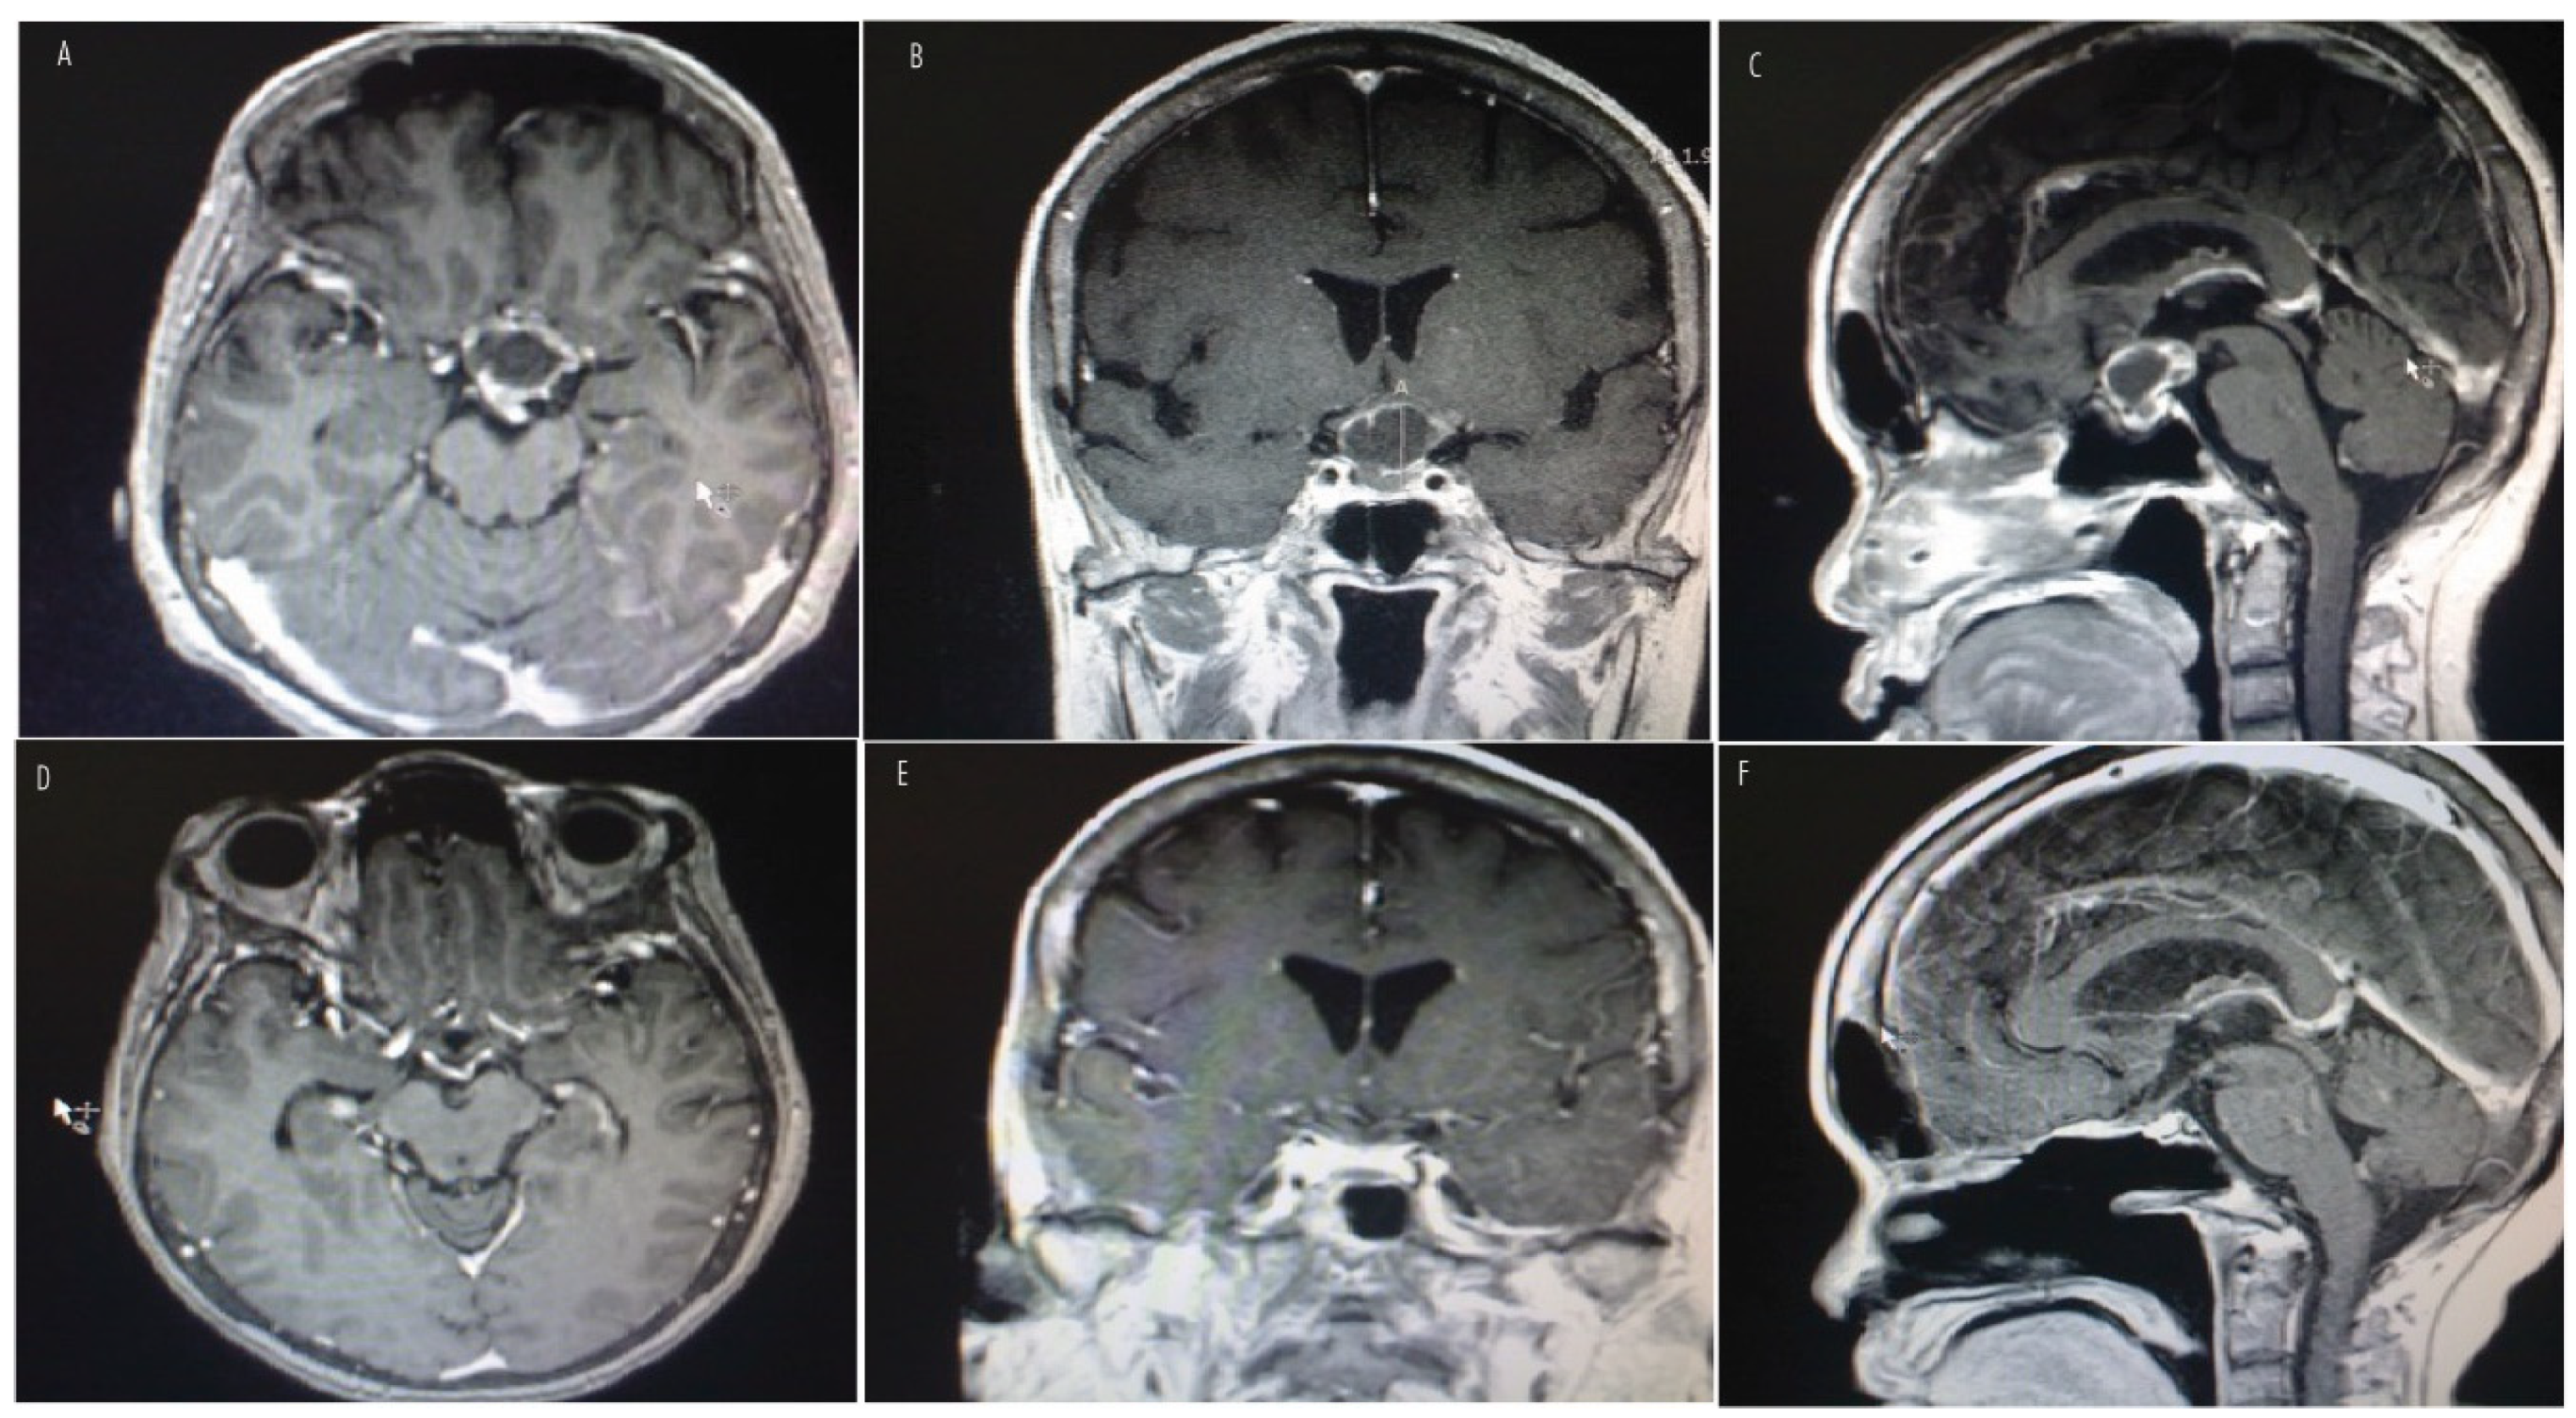

7. Histopathologic Features and Radiologic Features